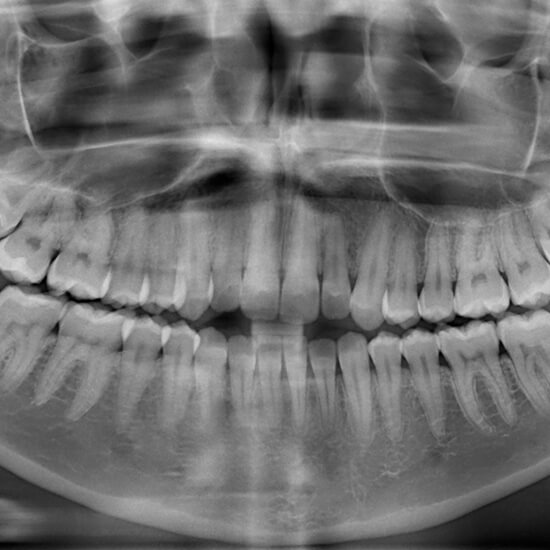

Digital X-rays have revolutionized insight into a patient’s oral health. Digital X-rays can detect a wide range of conditions but are commonly used to identify bone fractures, dental issues, and misalignment. At your appointment, what our dentist can detect will vary on the type of dental X-ray taken. For example, panoramic X-rays provide an entire view of the mouth in a single image, while a bitewing dental X-ray shows the upper and lower teeth in one area of the mouth.